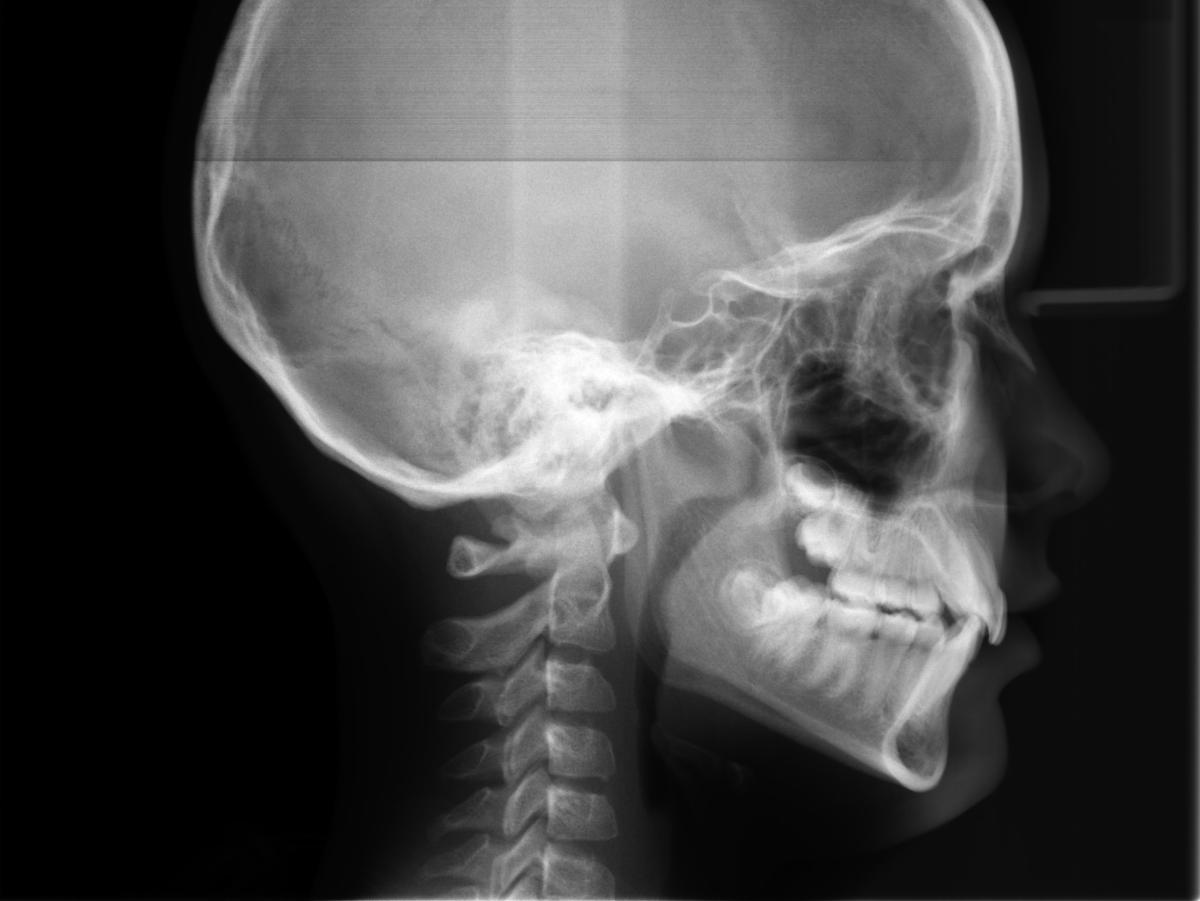

For our x-ray series, we've saved the best for last. If you've had an orthodontic consult, you may have taken a Cephalometric X-Ray, or "ceph," displayed below!

A single ceph image can tell us a lot of information. In dentistry, specifically orthodontics, cephs are used to check a patient's bite, also known as occlusion, as well overjet and overbite. These x-rays assist orthodontists in creating treatment plans to create a healthy and comfortable bite.

This is not the only thing cephs can tell us, though! This specific x-ray can also show us where the patient is in their stage of growth. Do you see the vertebrae in the x-ray above? Each one has a bit of a curve to it towards the bottom: this indicates the end of this patient's growth stage! If the vertebrae are more squared off, the patient is still experiencing stages of growth, which you can see in the example below.